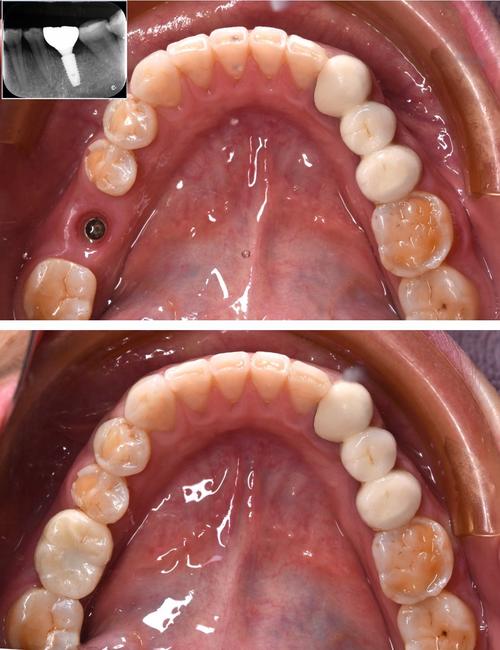

材料与工艺:甲类种植体多采用四级纯钛(钛含量≥99.75%)或钛合金(如Ti-6Al-4V),生物相容性极佳,能与人体骨骼形成牢固的“骨结合”(种植体与牙槽骨直接融合,无软组织间隔),其表面处理技术是核心竞争力,如Straumann的SLActive活性表面、Nobel的TiUnite表面,通过喷砂酸蚀、阳极氧化等工艺,形成微米级粗糙结构,促进成骨细胞附着,将骨结合时间从传统的3-6个月缩短至4-8周,甚至实现即刻负重(植入后短时间内安装牙冠)。

适应症与优势:甲类种植体适用范围极广,尤其适合牙槽骨条件差(如骨量不足、骨密度低)、需要即刻种植/即刻负重、全口/半口种植等复杂病例,其长期临床成功率高达98%以上,10年留存率超95%,且能更好地应对咬合力大、后牙区负重需求高的场景,这类品牌通常提供完善的终身质保服务,售后体系成熟。

材料与工艺:乙类种植体同样以纯钛(多为三级钛或四级钛)为主要材料,生物相容性良好,骨结合成功率与甲类接近(长期成功率95%以上),表面处理技术虽不及甲类顶尖,但已相当成熟,如Osstem的SA表面(喷砂酸蚀)、Dentium的SLA表面,能有效促进骨细胞生长,骨结合时间约3-4个月,部分高端型号(如登腾的Xive、奥齿泰的TSIII SA)也具备亲水表面技术,可缩短骨结合周期。